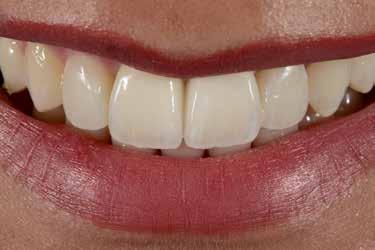

A front régióban alkalmazott minimál invazív multidiszciplináris megközelítés eredményeként jelentős mértékben tudtuk javítani a páciens esztétikai megjelenését. A beavatkozások során japán washi papír felhasználásával történő belső fogfehérítést, valamint háromdimenziós nyomtatással készült sebészeti sablon által vezetett ínyplasztikát végeztünk, majd az esztétikai zónában lévő fogakat – köztük egy elszíneződött nagymetsző fogat – ultravékony földpátkerámia héjakkal láttuk el.

A páciens elsősorban a mosolyának megjelenésén szeretett volna javítani. Egy előzetes állapotfelmérést követően az elszíneződött fog belső fehérítését, ínyplasztikát, valamint a felső front- és első kisőrlőfogak esztétikai célú helyreállítását javasoltuk. A belső fogfehérítés során nátrium-perborát és 30%-os hidrogén-peroxid keverékével átitatott washi papírt alkalmaztunk. Az anyag pulpakamrába történő helyezését követően az üreget üvegionomer cementtel zártuk. A fogfehérítés befejezését követően 3D nyomtatott sebészi sablont készítettünk, majd a felső front régióban megfigyelhető lágyrészek lefutását ezen sablon segítségével korrigáltuk. A sebészi beavatkozást követően 6 hónappal ultravékony földpátkerámia héjakat készítettünk.

A páciens elégedett volt a végleges restaurátumok színével, formájával és méretével. A kezelés végeredménye kielégítette az esztétikai elvárásait (9. ábra). A frissen átadott restaurátumok épségének megőrzése érdekében a páciens számára éjszakai fogvédősínt készítettünk. A páciensünk a négyéves kontrollvizsgálat során is nagyon elégedett volt a kezelés eredményével. A korábban meglévő fekete háromszögek eltűnésének különösképpen örült (9. és 10. ábrák)

Jelen esettanulmányban három meglévő technika kombinálását és továbbfejlesztését mutattuk be: washi papír használatával történő belső fogfehérítést, nyomtatott sebészi sablon által vezetett ínyplasztikát, és a fogakra ultravékony földpátkerámia héjakkal történő ellátását. E bonyolult eset kezelése során – minimálinvazív megközelítés mellett – kiemelkedő esztétikai eredményt sikerült elérni.

Az alapos tervezést követően végzett restauratív beavatkozások során sikeresen kombináltuk a washi papírral végzett belső fogfehérítést, a 3D nyomtatott sebészeti sablonnal és elektrokauterrel végzett ínyplasztikát, továbbá az ultravékony földpátkerámia héjakkal történő ellátást. A kezelési terv követésével el lehetett érni a kívánt esztétikai eredményeket, amelyek már 4 éve stabilnak bizonyultak.